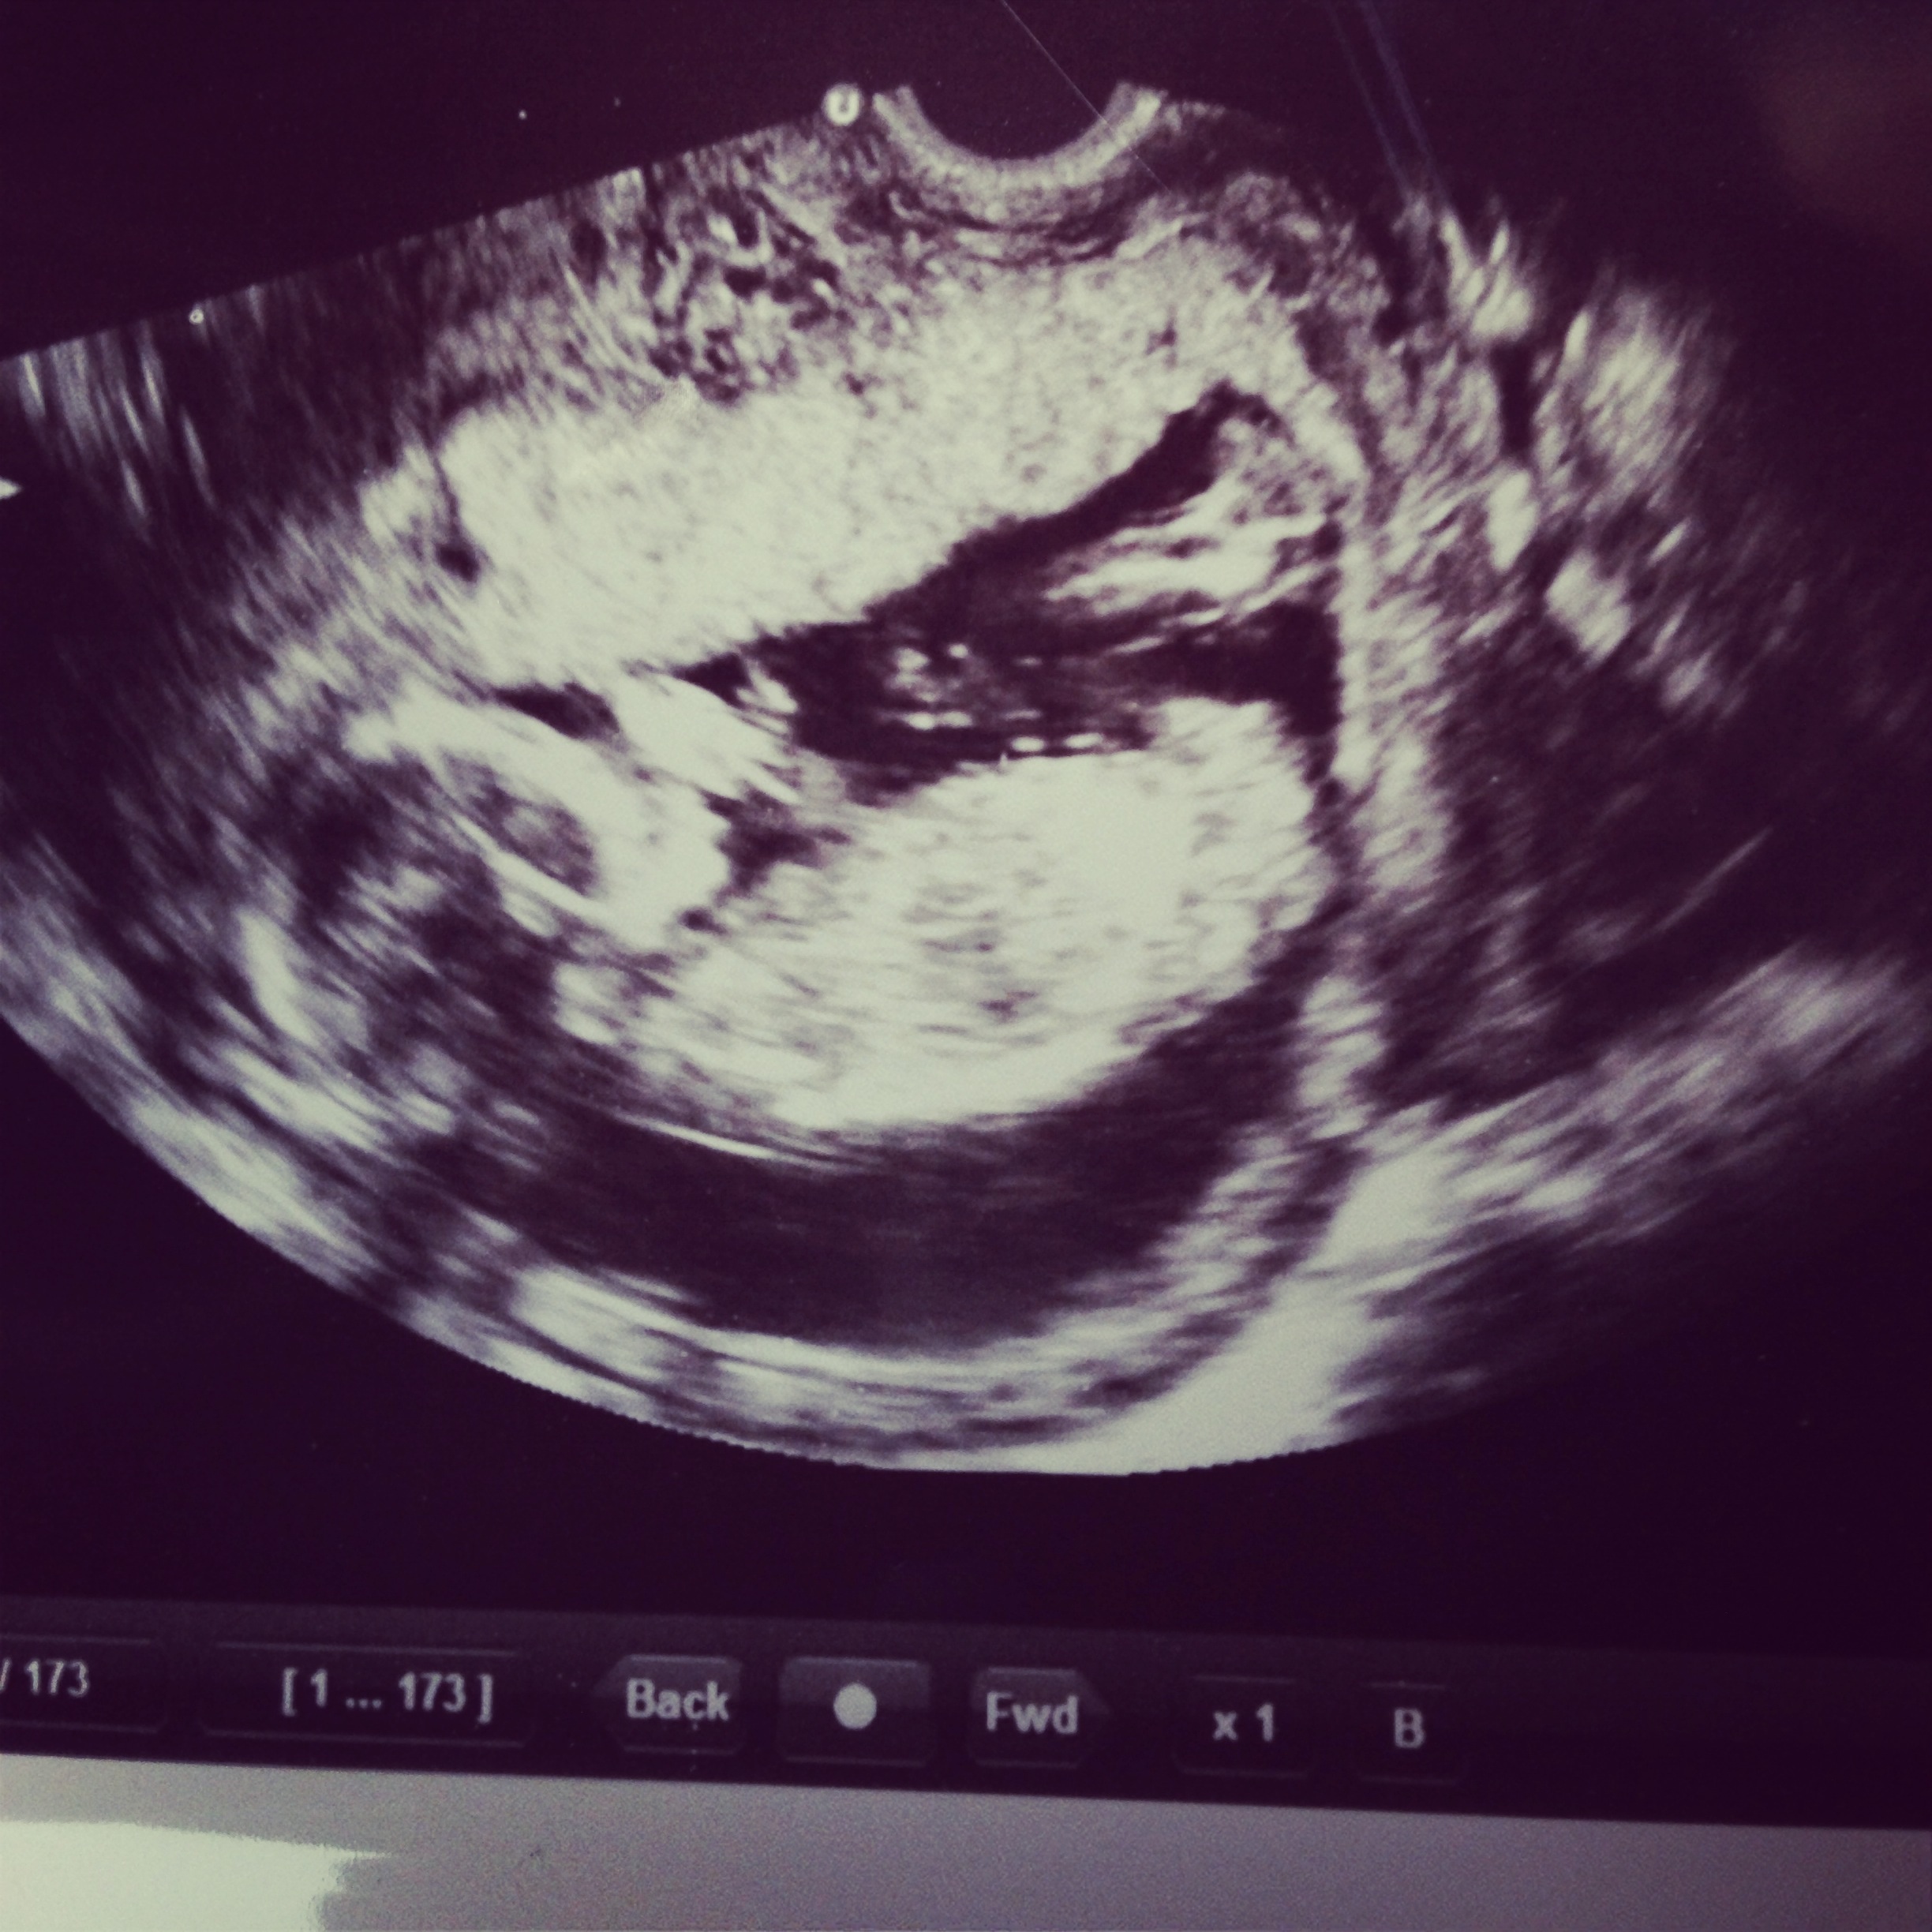

Attachment 16858I'm 15 weeks and 3 days pregnant. Based on the skull theory can you tell if boy or girl? :running: